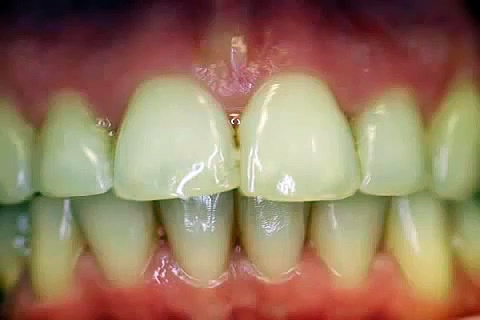

Die Krone ist der obere Anteil eines Zahnes, der aus dem Zahnfleisch herausragt. Die Zahnkrone ist meist ein im Labor hergestellter Zahnersatz, man unterscheidet Keramikkronen von Metallkeramischen Kronen. Häufig nimmt man das Material, welches verwendet wurde für die Bezeichnung, so z.B. bei Zirkonkronen. Diese Zahnkronen bestehen also aus Zirkoniumdioxid. Für Sie sind solche Bezeichnung irreführend, denn die Qualität einer Krone hat nichts mit dem verwendeten Material zu tun, auch nicht der Preis der Krone. Alle Materialien müssen biologisch getestet sein und sind unterlaufen ein strenges Prüfungsverfahren. Wieso bei manchen Kronen das Zahnfleisch zurück geht hat was mit dem Beschliff des Zahnstumpfes und dem Zahnabdruck selbst zu tun. Verursacht eine Zahnkrone Zahnfleischbluten und/oder Zahnfleischrückgang, dann ist die Krone in der Regel undicht und gehört einfach wiederholt. Leider werden dem Patienten häufig Ausreden wie „Allergie" oder „Unverträglichkeiten" genannt, das ist aber unwahr, mehr dazu im Video Hohlkehlenbeschliff.